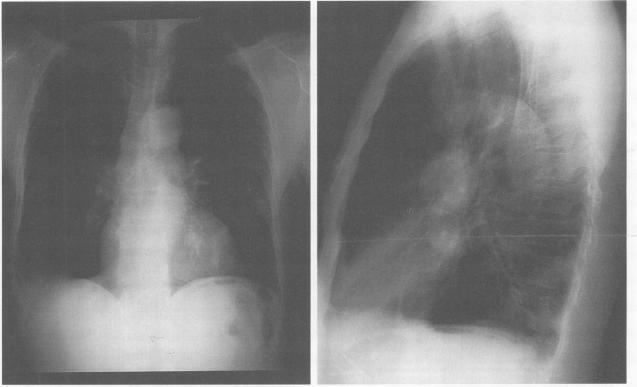

Sarcoidosis is a multisystem granulomatous disorder of unknown cause that presents most frequently in young adults with bilateral hilar adenopathy, pulmonary infiltrates, and skin or eye lesions. The multisystem clinical manifestations of this disease are a diagnostic challenge to all physicians. Although the clinical and pathologic characteristics of sarcoidosis are well described, the decision to treat and the optimal therapy are less well defined. This review focuses on the natural history, clinical manifestations, controversies in therapy, including steroid-sparing agents, and current concepts of how the disease's activity can be monitored.

结节病是一种病因不明的多系统肉芽肿性疾病,最常见于年轻成年人,表现为双侧肺门淋巴结肿大、肺部浸润以及皮肤或眼部病变。该疾病的多系统临床表现对所有医生来说都是一个诊断挑战。尽管结节病的临床和病理特征已有详尽描述,但关于治疗决策和最佳治疗方法的界定却不够明确。本综述聚焦于结节病的自然病程、临床表现、治疗方面的争议(包括糖皮质激素节省剂)以及目前关于如何监测该疾病活动的理念。